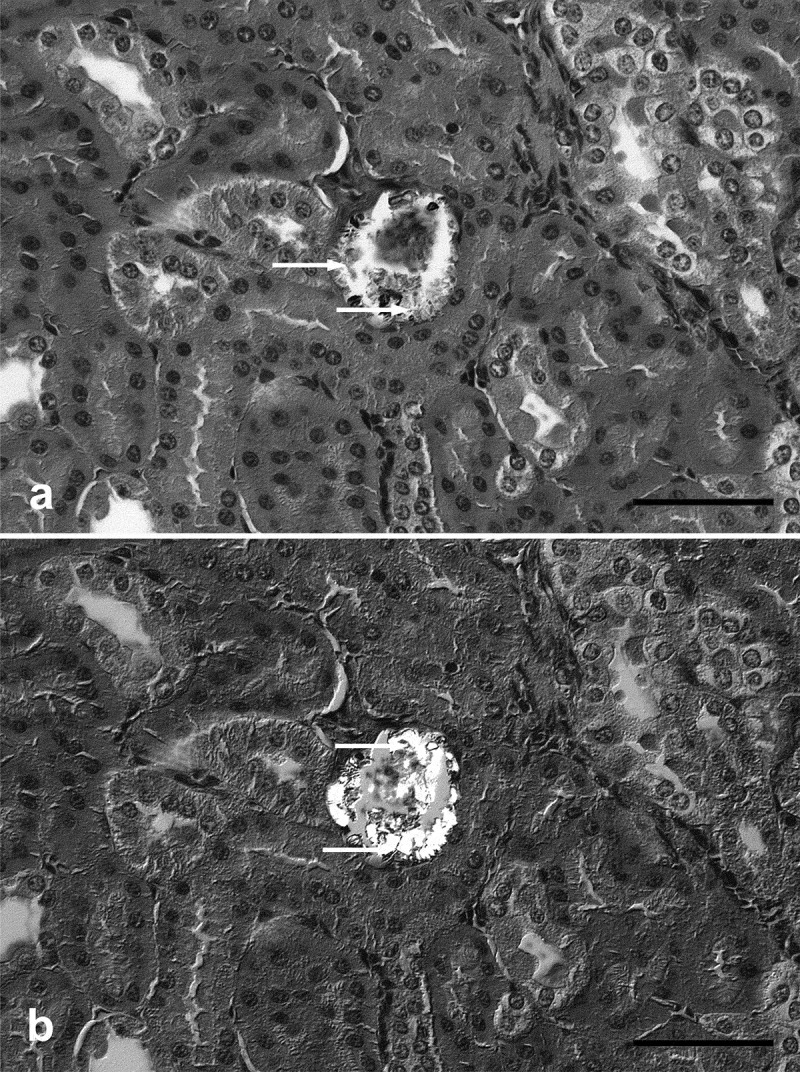

我们报告在尼日利亚西南部伊巴丹偶然观察到的非洲果蝠(Epomops franqueti)可能自发的草酸盐肾病病例,在该物种的解剖和血清学调查中。对野生捕获的蝙蝠进行镇静、心内灌注、尸检和组织病理学检查。所有15只野生捕获的非洲果蝠显然都很健康。然而,光镜显示轻度少灶小管肾病伴腔内偏光晶体沉积,一例被解释为亚临床草酸盐肾病。总之,我们建议饮食病因学,基于高抗坏血酸或草酸含量水果的季节性可用性。然而,不能完全排除接触人为污染物的可能性。

ABSTRACT We report a possible spontaneous case of oxalate nephrosis in an African fruit bat (Epomops franqueti), incidentally observed in Ibadan, South-West Nigeria, in an anatomical and serological survey of the species. Wild caught bats underwent sedation, intracardial perfusion, necropsy and histopathology. All 15 wild-caught African fruit bats were apparently healthy. However, light microscopy revealed mild oligofocal tubulonephrosis with intraluminal deposition of polarizing crystals interpreted as subclinical oxalate nephrosis in one case. In summary, we suggest a dietary aetiology, based on seasonal availability of high ascorbic acid or oxalate containing fruits. However, exposure to anthropogenic contaminants cannot be completely ruled out.